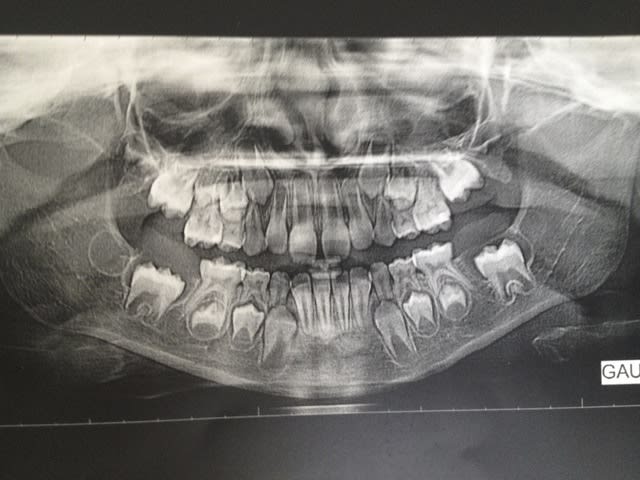

voilà une jeune fille qui n'a rien demandé à personne mais qui a un souci d'évolution des 36 et 46

Vue il y a 3 ans à l'âge de 8 ans, avec un retard d'évolution de 36 et 46 et une agénésie de 25. ( premier OPT). Les parents devaient repartir au pays donc "on verra".

Malheureusement disparue pendant 3 ans, je l'a revoie au mois de juillet à 11 ans donc.

pas d'évolution des 36 et 46 et pas d'évolution non plus des germes de 45 et 35

Il y a quand même eu une édification radiculaire des 6 et une migration, certes elle n'est pas très importante compte tenu de la durée écoulée.

Sur les 2 panos, on voit quand même une bonne épaisseur de gencive. Une gencive fibreuse fait partie des causes de retard d'éruption même si pour les molaires c'est pas le plus fréquent.

Par contre pour 35 et 45, elles n'ont pas bougé. Vu leur édification radiculaire, il faut bien protéger 75 et 85 car à ce rythme là elle va les conserver longtemps et je ne vois pas ce qui pourrait les forcer à se presser.

Le retard pour les 7 est pas mal non plus.